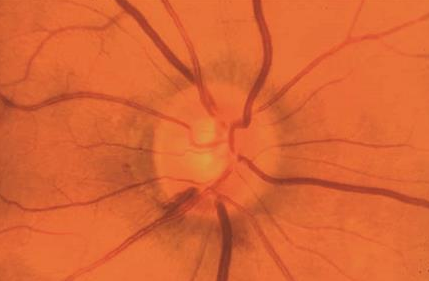

Expected ON appearance with given defect?

HVF: dense superior arcuate defect OD

inferior notch

frequently observed in what condition

low-tension glaucoma

(disc heme seen IT)